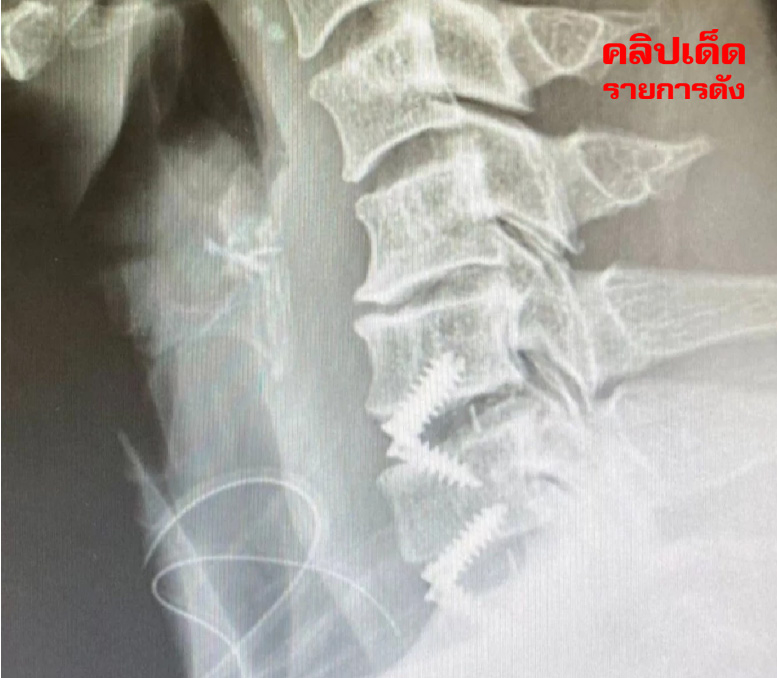

นักร้องชื่อดังชาวไทยได้แสดงออกถึงประสบการณ์และความเสี่ยงที่เกี่ยวกับการผ่าตัดดังกล่าวอย่างละเอียด ตูน บอดี้สแลม หรือ อาทิวราห์ คงมาลัย ได้รับการผ่าตัดจากทางด้านหน้าลำคอเพื่อเปลี่ยนหมอนรองกระดูกทั้งสองข้อที่มีปัญหาออกและแทนที่ด้วยหมอนรองกระดูกเทียม

โดยยึดติดกระดูกทั้งสามข้อให้เป็นเหมือนกระดูกข้อเดียว เพื่อลดความเสี่ยงที่จะเกิดข้อจำกัดในการก้มหรือเงยของคอเมื่อผ่าตัดเสร็จสิ้น การผ่าตัดลักษณะนี้ได้รับการเตรียมการและการดูแลอย่างใกล้ชิดจากทีมแพทย์และพยาบาลที่ร่วมงาน การพักฟื้นหลังจากการผ่าตัดนี้ก็เป็นช่วงที่ตูน บอดี้สแลม